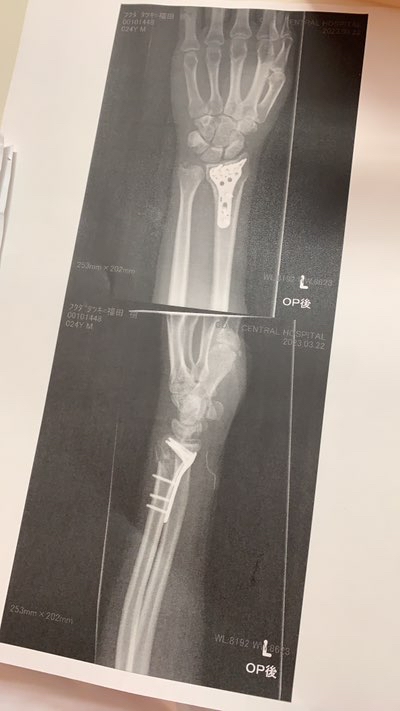

次の日、自分の不注意でまさかの橈骨骨折

全治3ヶ月となり俺の春爆は終了しました